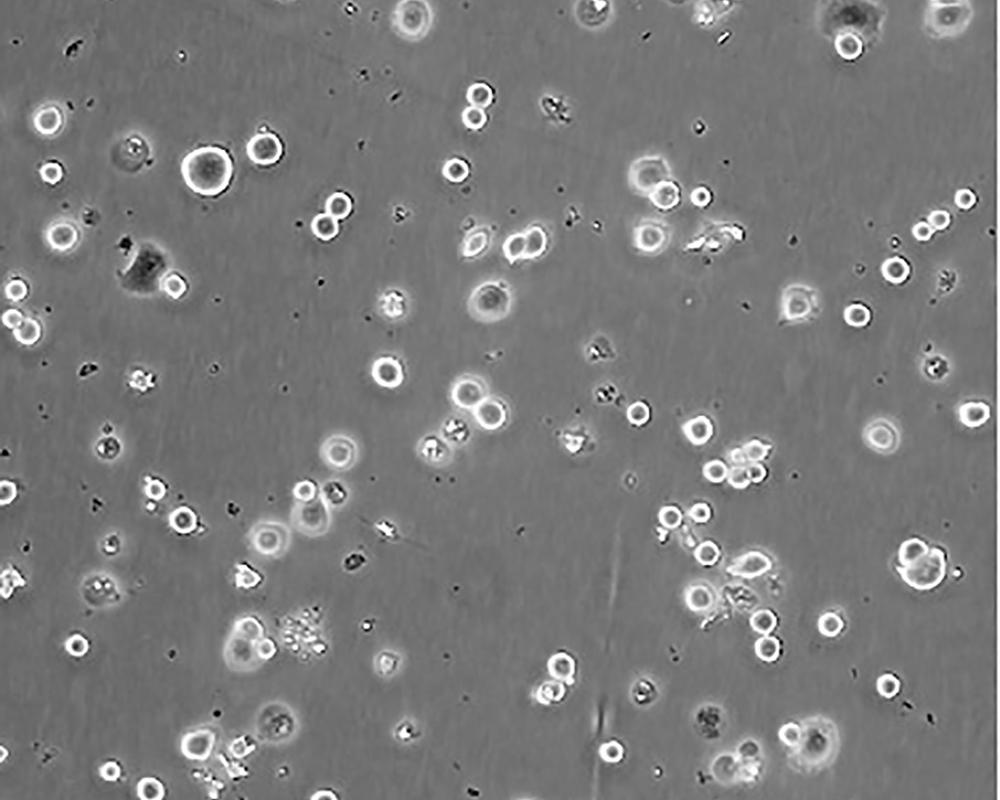

生長特性 adherent

形態特征 epithelial

細胞描述 he patient, a White, Caucasian female, age 43, blood type A+, had been treated with radiation, steroids, cytoxan and 5-fluorouracil.No virus particles.Ultrastructural features include microvilli and desmosomes, glycogen granules, large lysosomes, bundles of cytoplasmic fibrils.The SKBR- 3 cell line overexpresses the HER2/c-erb-2 gene product.

細胞傳代步驟 如果細胞密度達80%-90%,即可進行傳代培養。1. 棄去培養上清,用不含鈣、鎂離子的PBS潤洗細胞1-2次。2. 加2ml消化液(0.25%Trypsin-0.53mM EDTA)于培養瓶中,置于37℃培養箱中消化1-2分鐘,然后在顯微鏡下觀察細胞消化情況,若細胞大部分變圓并脫落,迅速拿回操作臺,輕敲幾下培養瓶后加少量培養基終止消化。3. 按6-8ml/瓶補加培養基,輕輕打勻后吸出,在1000RPM條件下離心4分鐘,棄去上清液,補加1-2mL培養液后吹勻。4. 將細胞懸液按1:2到1:5的比例分到新的含8ml培養基的新皿中或者瓶中